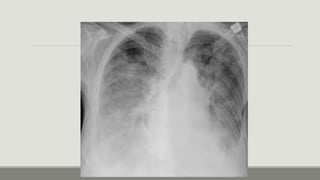

Rx de tórax

Fase

alveolar:

Patrones alveolares mal definidos, confluentes, con

distribución parcheada, bordes irregulares y

predominante en el tercio interno del pulmón,

patrón en ¨alas de mariposa’ (la consolidación se

extiende desde la región perhiliar hacia afuera,

dejando no daño a la zona subpleural)

Rx de tórax Fase alveolar: Patronesalveolares mal definidos, confluentes, con distribución parcheada, bordes irregulares y predominante en el tercio interno del pulmón, patrón en ¨alas de mariposa’ (la consolidación se extiende desde la región perhiliar hacia afuera, dejando no daño a la zona subpleural)